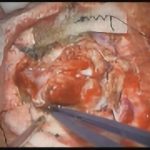

術中写真

摘出 前